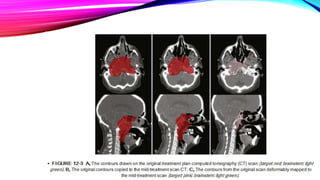

OFFLINE ADAPTATION • Theimaging system used : Conventional CT scanner or an in-room CT scanner. • The adaptation can be triggered by : • As a protocol (for example after 20 and 40Gy delivered dose), • Clinical observations of masks not fitting, weight loss, or other surface changes, or by changes observed on an in-room imaging system

• The rationale- substantial shrinkage of the tumor/weight loss throughout the course of therapy, between the anatomy at the time of the original CT scan and the cone beam CT scans acquired during treatment. Planning CT After 16# After 25#